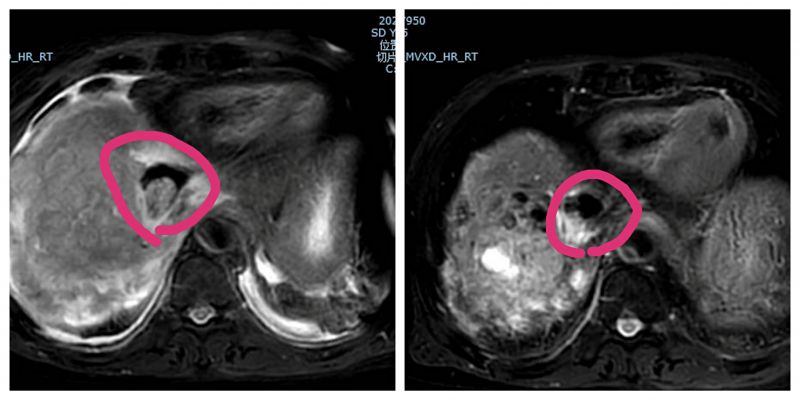

经过放疗团队的共同协作及患者和家属的积极配合,一个半月后,张大爷的病情得到了明显缓解,表现为食欲明显好转,未再出现上腹部胀痛不适,肿瘤AFP由高峰期的3698 ng/mL降至609 ng/mL,复查肝脏增强MRI提示下腔静脉、右心房癌栓明显消退,解除了瘤栓脱落引起肺动脉栓塞的“不定时炸弹”风险。同时,肝右叶巨大肿瘤明显缩小,而放疗治疗野外的病灶保持稳定。张大爷的老伴高兴地说:“他原来经常卧床,没劲下床活动,现在都能赶黄务大集了。”得知复查结果超出预期,张大爷自己也忍不住喜极而泣,连连感谢所有医护人员。

放疗前(左)后(右)肝右叶瘤灶对比